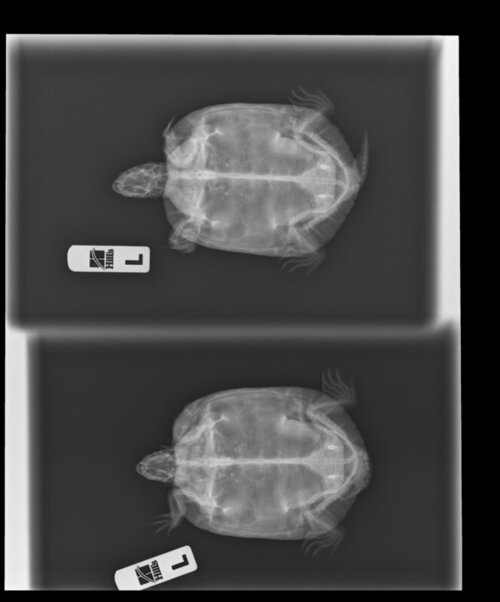

Антон123 Ваше имя: Антон Локация: Москва Опубликовано: 7 апреля 2022 Опубликовано: 7 апреля 2022 1. Москва, 36 2. Красноухая. 3. Содержится в аквариуме Размер жилища большой, в литрах не мерил, см.фото 4. Лампа накаливания в качестве точки прогрева установлена, работает по таймеру с 9 до 21. Ультрафиолетовая лампа UVB10 SimpleZooBulk месяц как менял. Работает с 9 до 21. 4.3. Берег есть 4.4 фильтр для воды, внутренний 4.5. Нагреватель воды установлен 5. Грунта нет 6. Температура воды 26, на бережке под лампой 33 7. Ест 2 раза в неделю, в основном нежирную рыбу. Подкормки есть, но давно не давал 8. Возраст 5-6 лет, вес 370грам, длина панциря 14см В чём проблема/болезнь? Как давно проявилась? Сидит на берегу, чаще всего с закрытыми глазами. Вялая. Состояние такое уже 2-3 недели. Плавает без крена. От еды до сегодняшнего дня не отказывалась. Сегодня уже и ела совсем чуть-чуть и еле-еле. 9. Приезжала врач, рекомендовала сделать рентген, на всякий случай уколола кальций и оставила еще, чтобы мы кололи через день. Рентген приложил здесь, фото всего остального по ссылке ниже 10. https://postimg.cc/gallery/8zGcDFG

Антон123 Ваше имя: Антон Локация: Москва Опубликовано: 7 апреля 2022 Автор Опубликовано: 7 апреля 2022 (изменено) А нет. Шприц на 1мл. 50 делений. Вот 2,5 таких деления. Получается 0,02*2,5=0,05 И! Забыл написать в самом начале. Пару дней назад черепаха зависла не шевелясь в воде с открытым ртом и так и висела. А когда доставал ее на сушу, она бодро бежала назад в воду. И было ощущение, что она не может уходить на дно Также на самом нижнем рентгеновском снимке мне кажется что-то не то в нижней части черепахи. Изменено 7 апреля 2022 пользователем Антон123

Консультанты moth Ваше имя: Мария Локация: Москва Опубликовано: 8 апреля 2022 Консультанты Опубликовано: 8 апреля 2022 @Антон123 пока нет по этим снимкам нельзя понять есть проблемы с лёгкими или нет, нужны другие проекции